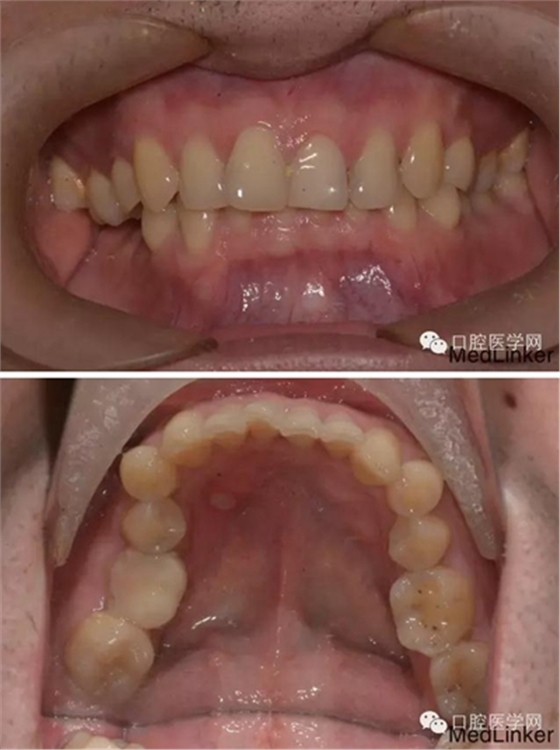

【病例情況】

主訴:修復前要求正畸現(xiàn)

病史:因右下第一磨牙慢性牙髓炎于本院牙體牙髓科行根管治療,因牙體缺損大,建議全冠修復,修復科醫(yī)師檢查后發(fā)現(xiàn),因右上后牙伸長,導致右下磨牙修復合齦間隙不足。(就這樣的情況大家都是怎么做呢?對合第一磨牙根管治療后截冠嗎?)

【查體】

檢查:口內恒牙列,上頜牙弓寬于下頜,右側第一磨牙第二磨牙正鎖合右下第一磨牙合面見大面積牙色充填物,牙面磨耗嚴重,咬合緊。